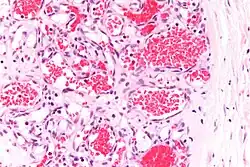

![]() | Renal cell carcinoma | Micrograph of clear cell renal cell carcinoma showing cells with clear cytoplasm, typically arranged in nests and nuclear atypia. | Category: Histopathology of renal cell carcinoma | Renal cell carcinoma |